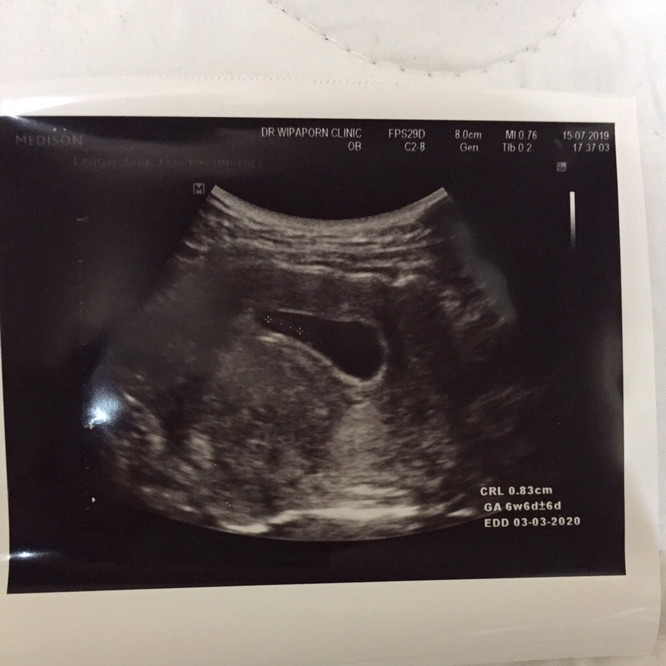

คือ ตอนนี้ท้องได้ 6 สัปดาห์ค่ะ หมออัลตราซาวน์ เมื่อตอน 5 สัปดาห์ ไม่เจอน้อง อาการเจ็บหน้าอกก็ลดลงมาก

ของเรามีแต่ถุงตั้งครรภ์ ค่ะ 6 wk